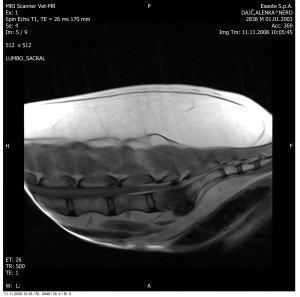

Slika: Primer vnetega medvretenčnega diska